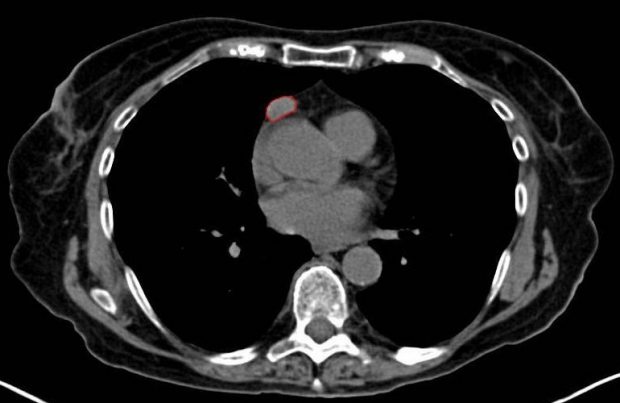

Die sogenannte Partikelbestrahlung ist bei einigen Krebsarten die erfolgsversprechendste Behandlungsmethode. Dabei werden Protonen oder Ionen auf zwei Drittel der Lichtgeschwindigkeit beschleunigt und auf eine bestimmte Stelle des Körpers gerichtet. Dort wird dann Energie freigesetzt, wodurch die Tumorzellen zerstört werden. Damit die Therapie so erfolgreich wie möglich ist, ist es von entscheidender Bedeutung, im Vorfeld möglichst viele Informationen über den Tumor zu sammeln. Bisher werden dafür vor allem die Computertomografie (CT) und die Magnetresonanztomografie (MRT) genutzt. Beide Verfahren ermöglichen es, 3D-Aufnahmen aus dem Innenleben des Körpers anzufertigen, wodurch der Tumor genau lokalisiert werden kann. Forscher an der FH Wiener Neustadt wollen nun aber noch einen Schritt weiter gehen: Sie hoffen, mithilfe von speziellen Biomarkern auch mehr über die innere Beschaffenheit des Tumors erfahren zu können. Foto: Cynthia Goldsmith CC BY-SA 3.0 (VIA WIKIMEDIA COMMONS) Radioisotope machen die entscheidenden Informationen sichtbar Beispielsweise ist es für die genaue Ausrichtung der Bestrahlung und die korrekte Dosis wichtig zu wissen, wo sich die Zellen des Tumors am schnellsten teilen. Genau dies wollen die österreichischen Forscher zukünftig mit einem einfachen Trick sichtbar machen. Dafür machen sie sich die Tatsache zunutze, dass dort, wo sich die meisten Zellen teilen, auch am meisten Energie verbraucht wird. Diese wiederum wird in Form von Zucker – also Glukose – zugeführt. Die Forscher haben nun ein Verfahren entwickelt, bei dem Glukosemoleküle mit einem Radioisotop versehen werden. Dadurch kann der Weg der Moleküle und deren Interaktion mit der Umgebung innerhalb des Körpers nachvollzogen werden. Letztlich wird dadurch dann auch sichtbar, wie sich die Glukose innerhalb des Tumors verteilt. Oder anders ausgedrückt: Wo am meisten Energie verbraucht wird – und sich somit am meisten Zellen teilen. Noch ist das Verfahren nicht reif für den Praxiseinsatz Der selbe Grundsatz lässt sich zudem auf andere Stoffwechselprozesse innerhalb des Tumors übertragen. So kann auf diese Weise beispielsweise auch die Sauerstoffversorgung oder die Aktivität von bestimmten Aminosäuren sichtbar gemacht werden. Auch dies kann helfen, die Bestrahlung zu optimieren. Angst vor einer zu großen radioaktiven Belastung muss der Patient dabei nicht haben: Die Radioaktivität ist nicht höher als bei einem Transatlantikflug. Allerdings dürften noch einige Jahre ins Land ziehen, bis die Methode standardmäßig zum Einsatz kommt. Denn aktuell ist es noch sehr schwierig, aus der Masse an Rohdaten die für die Tumorbehandlung relevanten Aspekte herauszufiltern. Dafür werden spezifische mathematische Modelle benötigt, die aktuell noch ausgearbeitet werden. Erste Tests bei Tieren verliefen aber schon vielversprechend. Via: Der Standard Teile den Artikel oder unterstütze uns mit einer Spende. Facebook Facebook Twitter Twitter WhatsApp WhatsApp Email E-Mail Newsletter